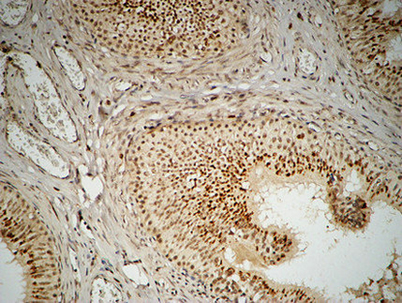

Product name: FEN-1 rabbit pAb

Dilutions: Western Blot: 1/500 - 1/2000. Immunohistochemistry: 1/100 - 1/300. Immunofluorescence: 1/200 - 1/1000. ELISA: 1/20000. Not yet tested in other applications.

Cellular localization: [Isoform 1]: Nucleus, nucleolus. Nucleus, nucleoplasm. Resides mostly in the nucleoli and relocalizes to the nucleoplasm upon DNA damage.; [Isoform FENMIT]: Mitochondrion .